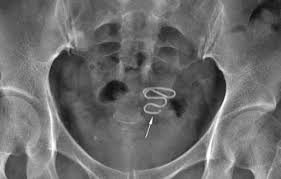

انواع اللولب بالصور

• ParaGard عبارة عن ملف ملفوف على سلك نحاسي، بمجرد وضعها ، ستعمل لمدة تصل إلى 10 سنوات.